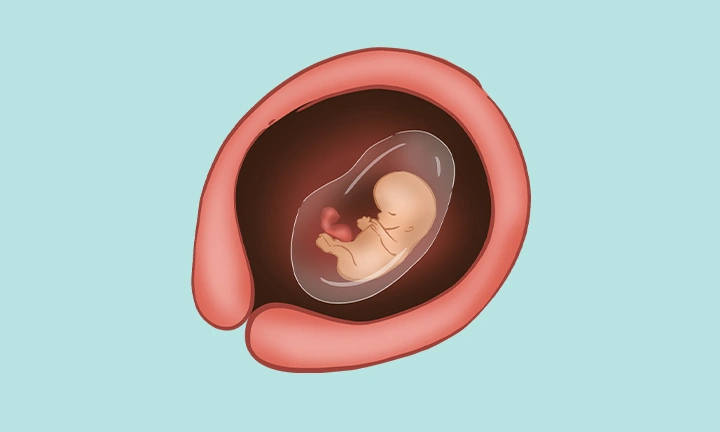

في الأسبوع العاشر من الحمل، لا يزال جنينك صغيراً، إلا أنه يخوض مرحلة نموّ سريع وواضح. إنه داخل السائل الأمنيوسي الدافئ والآمن، ويبلغ طوله حوالي ثلاثة سنتيمترات تقريباً. أصبح جسمه أكثر تناسباً— فلم يعد رأسه يبدو ضخماً مقارنة ببقية الجسم. تجوّفت مچاه وكواعبه، وأصابعه الصغيرة أصبحت واضحة للعين. إنّ تصور ذلك المخلوق الصغير الذي يكبر في داخلك يبعث شعوراً مدهشاً.

يمكن أن تكشف الأشعة فوق الصوتية أن الحويصلة الصفراوية (Yolk Sac) قد تراجعت، وأن الحبل السُري الذي يربط الجنين بالمشيمة أصبح واضحاً.

الأمعاء، التي كانت جزءاً من الحبل السُري، بدأت الانتقال إلى تجويف البطن وستُغطّى قريباً بالجلد.

نسيج الرئتين يتكوَّن، كما بدأت العظام الصغيرة حتى في أصابع اليد والقدم بالظهور. الخلايا الموجودة بداخل هذه العظام ستصبح قريباً مسئولة عن إنتاج خلايا الدم الحمراء – وهي مهمة كانت حتى الآن تقع على الكبد والطحال.

ملامح الوجه أصبحت أكثر وضوحاً، وربما تكون البراعم الأولى لـ أسنان الحليب قد بدأت التكوّن. يستطيع الجنين الآن فتح فمه وتحريك لسانه، وإن كان لا يمكنه التلويح بعد!